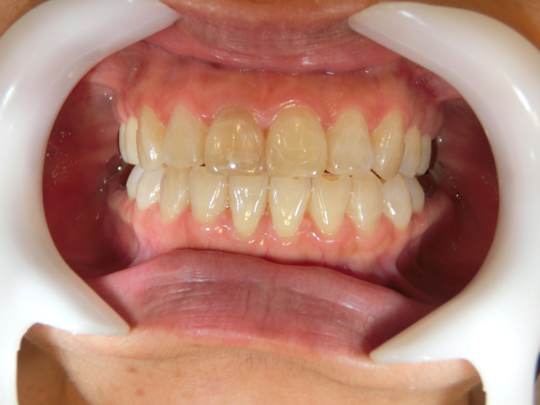

治療前

治療説明 歯科矯正でも目立ちにくい矯正方法であるマウスピース矯正で治療しました

治療期間 1年3か月

治療費用498000 円